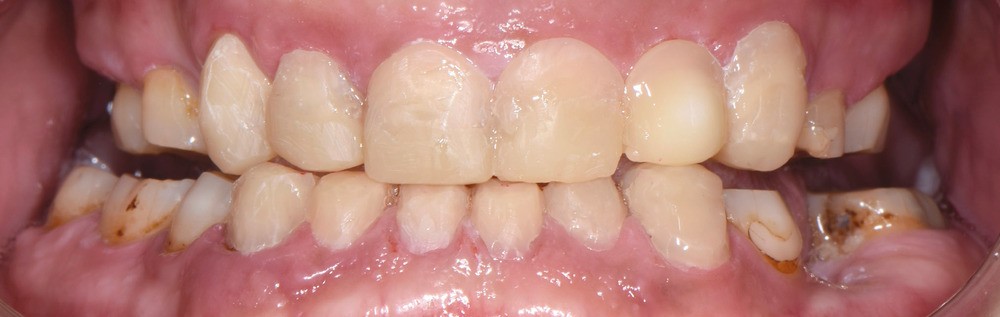

Au vu du contexte para-fonctionnel et de l’étendue de la perte tissulaire, des coiffes périphériques minimalement invasives ont été choisies afin de restaurer l’esthétique et la fonction. Actuellement, aucun consensus n’est fait sur le choix du matériau d’infrastructure à privilégier. Les matériaux hybrides usinables présentent des propriétés mécaniques, physiques et biologiques intéressantes en contexte d’usure sévère (e.g., module d’élasticité, résistance à la propagation de fêlures, facilité de réintervention). Une réhabilitation globale avec remontée de dimension verticale d’occlusion (DVO) par l’intermédiaire de coiffes composites renforcés en nano-céramiques est décrite.